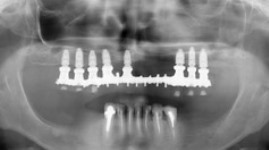

- Cas 2: vues panoramiques

AVANT REHABILITATION